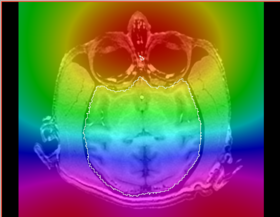

* Correction of the bias in vervet MRI. Acquisition parameters: 3T GE scanner, single-channel dedicated RF coil (Litzcage, Doty Scientific, Columbia, SC); 3D SPGR sequence (TI 600ms, TE 3.276ms, TR 15.28ms; flip angle 15 deg; matrix 256x256; FOV 12cm; in-plane resolution 0.47 mm; slice thickness 0.5 mm). | * Correction of the bias in vervet MRI. Acquisition parameters: 3T GE scanner, single-channel dedicated RF coil (Litzcage, Doty Scientific, Columbia, SC); 3D SPGR sequence (TI 600ms, TE 3.276ms, TR 15.28ms; flip angle 15 deg; matrix 256x256; FOV 12cm; in-plane resolution 0.47 mm; slice thickness 0.5 mm). | ||

- Correction of the bias in vervet MRI. Acquisition parameters: 3T GE scanner, single-channel dedicated RF coil (Litzcage, Doty Scientific, Columbia, SC); 3D SPGR sequence (TI 600ms, TE 3.276ms, TR 15.28ms; flip angle 15 deg; matrix 256x256; FOV 12cm; in-plane resolution 0.47 mm; slice thickness 0.5 mm).